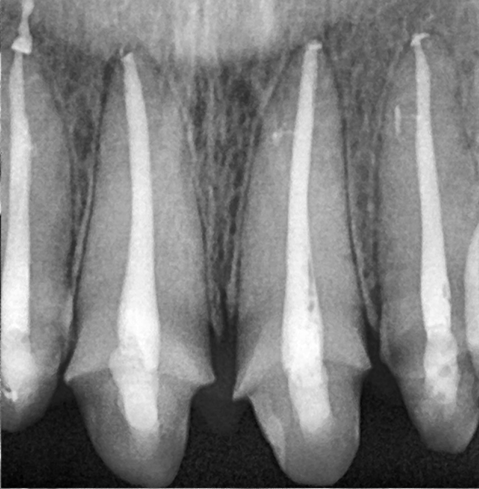

저희 병원에서는 고배율 내시경과

다양한 장비를 이용해

치근단 병소까지 정밀하게 확인하고,

치근관을 확실히 소독한 뒤

근관 충전 및 레진 코어,

지르코니아 크라운 복원까지

모든 과정을 체계적으로 마무리하였습니다.

앞니 신경치료가

깔끔하게 마무리 된 모습입니다!

파노라마상에서도 성공적으로

치료가 진행 된 모습을 체크하실 수 있습니다.